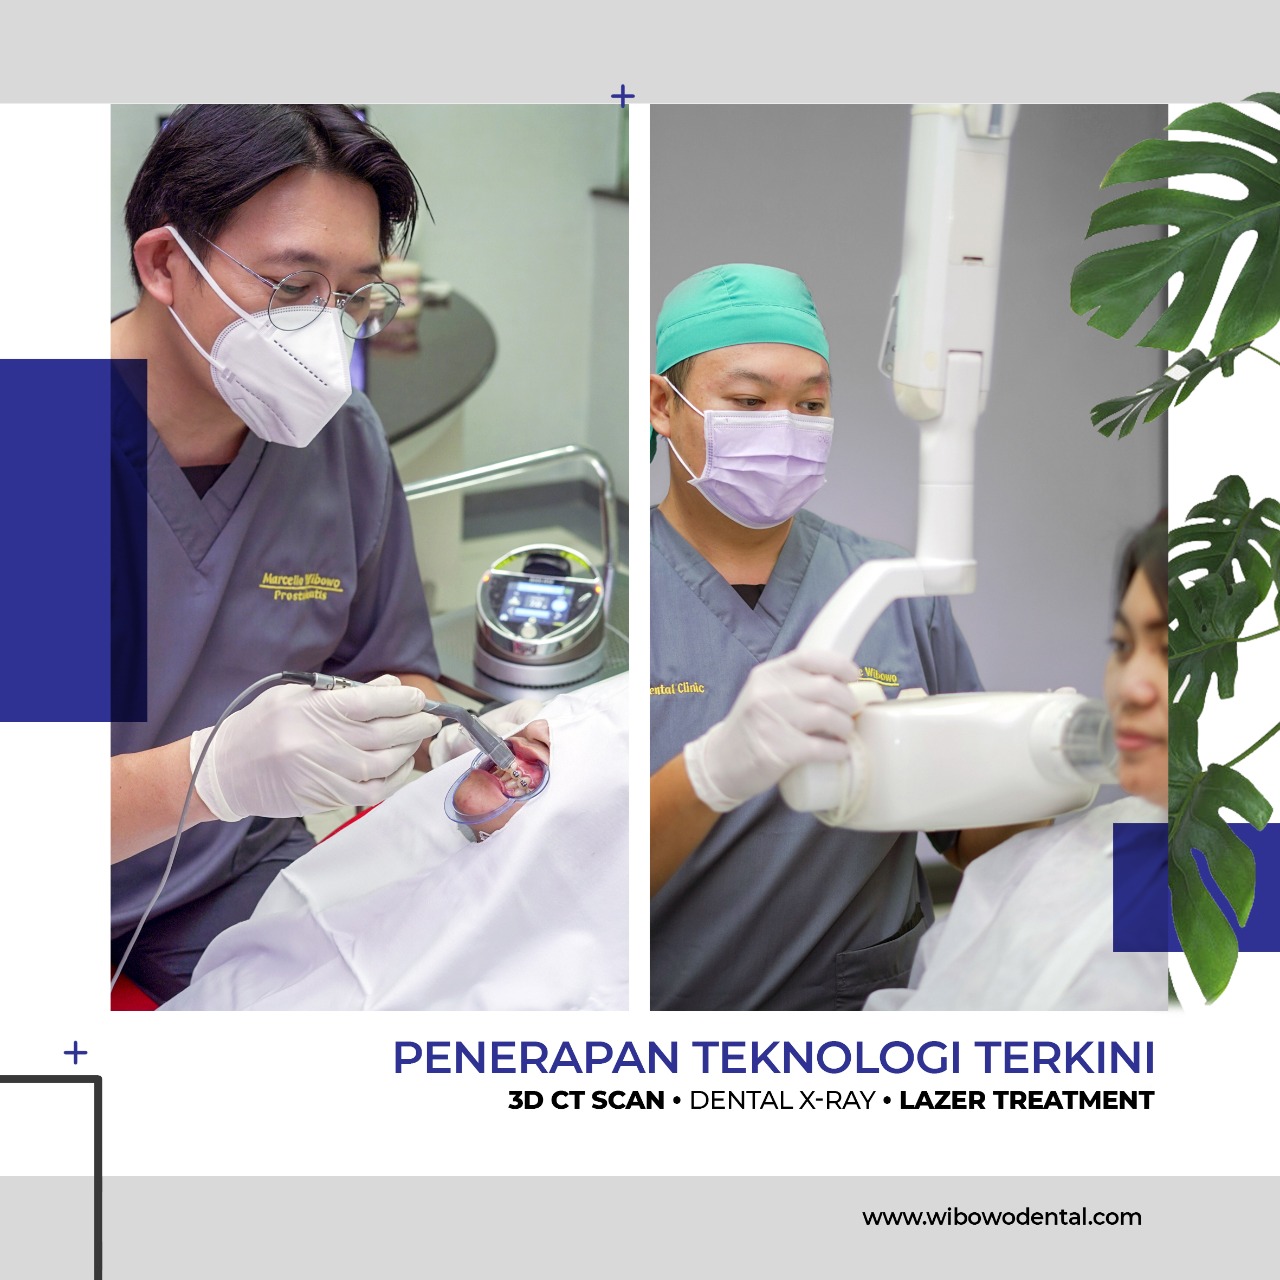

Eksis sejak tahun 1978, Wibowo Dental Clinic merupakan pionir Digital Dentistry di Surabaya. Mengedepankan perawatan yang terintegrasi dari tim dokter spesialis periodonsia, orthodonsia, dan konservasi gigi dan pengaplikasian teknologi terkini, Wibowo Dental Clinic telah dipercaya oleh berbagai kalangan, termasuk tokoh nasional.